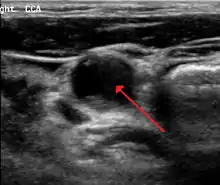

70 percent stenosis of the right internal carotid artery as seen by ultrasound. Arrow marks the lumen of the artery.

Carotid artery stenosis is usually diagnosed by color flow duplex ultrasound scan of the carotid arteries in the neck. This involves no radiation, no needles and no contrast agents that may cause allergic reactions. This test has good sensitivity and specificity.[8]

Typically duplex ultrasound scan is the only investigation required for decision making in carotid stenosis as it is widely available and rapidly performed. However, further imaging can be required if the stenosis is not near the bifurcation of the carotid artery.

One of several different imaging modalities, such as a computed tomography angiogram (CTA)[9][10][11] or magnetic resonance angiogram (MRA) may be useful. Each imaging modality has its advantages and disadvantages - Magnetic resonance angiography and CT angiography with contrast is contraindicated in patients with chronic kidney disease, catheter angiography has a 0.5% to 1.0% risk of stroke, MI, arterial injury or retroperitoneal bleeding. The investigation chosen will depend on the clinical question and the imaging expertise, experience and equipment available.[12]